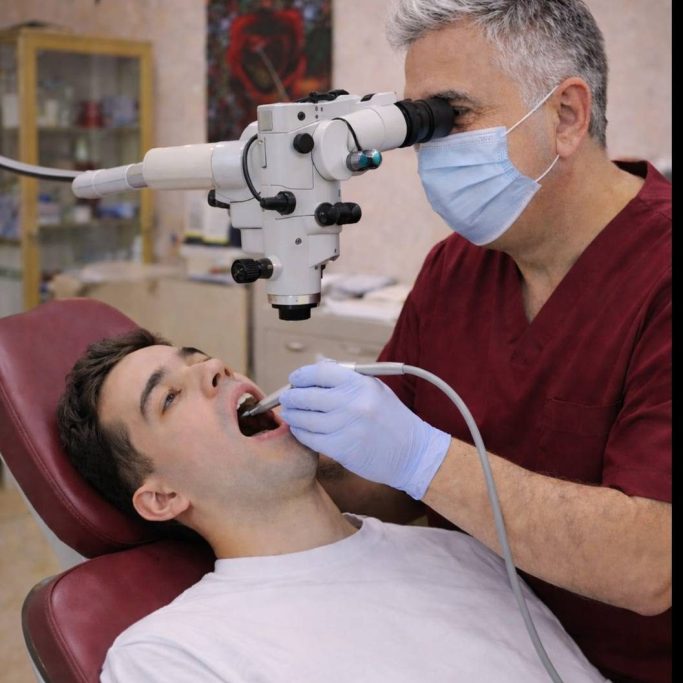

Entdecken Sie die Gesichter hinter MetaZahn! Unser erfahrenes Team aus Zahnärzten und Fachkräften steht Ihnen zur Seite, um die besten zahnmedizinischen Dienstleistungen zu bieten. Jeder Einzelne von uns bringt eine Fülle von Fachwissen, Leidenschaft und Engagement in unsere Arbeit ein, um sicherzustellen, dass Ihre zahnmedizinischen Bedürfnisse gründlich und einfühlsam betreut werden. Vertrauen Sie auf unsere Expertise und lassen Sie uns gemeinsam an Ihrem strahlenden Lächeln arbeiten.

In der heutigen Zeit bieten moderne Geräte eine Vielzahl an Behandlungsmethoden, die sowohl in der Medizin als auch in der Schönheitsindustrie Anwendung finden. Innovative Technologien wie Lasersysteme, digitale Diagnosetools revolutionieren die Art und Weise, wie Behandlungen durchgeführt werden. Diese modernen Geräte ermöglichen präzisere Eingriffe, schnellere Heilungsprozesse und oft auch minimal-invasive Verfahren, die den Patienten weniger belasten. Darüber hinaus verbessern sie die Effizienz der Behandlungen und bieten individuell angepasste Therapien, die auf die spezifischen Bedürfnisse jedes Einzelnen abgestimmt sind.